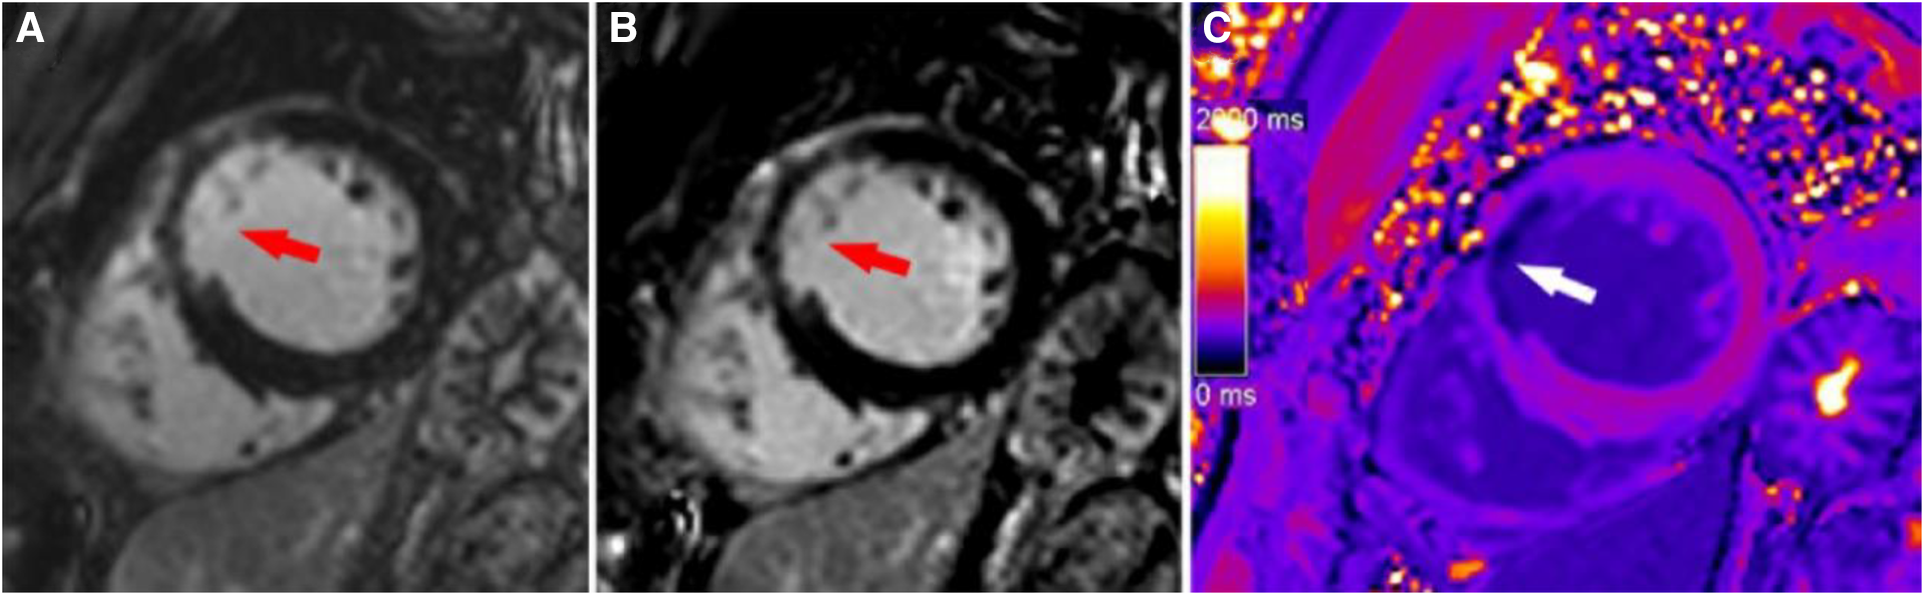

Figure 5

A typical case in which post-contrast T1 mapping improved transmural scar detection. A high-signal scar (red arrow) was observed on magnitude (A) and PSIR (B); however, poor contrast between the scar and blood hindered accurate delineation of the endocardial border and influenced assessment of the transmural extent of scarring. Post-contrast T1 mapping (C) provided greater border clarity (white arrow), improving the accuracy of assessment regarding the transmural extent of scarring.